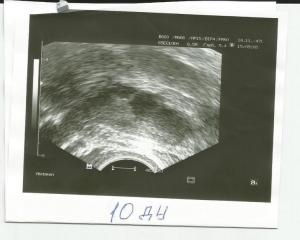

Овуляция( тесты на овуляцию)Добрый день! Помогите кто может разобраться! Сегодня 23 день цикла. Планируем ляльку. 7 месяцев назад была ВБ, удалили правую трубу. Сейчас как раз заработал левый яичник. На 10 ДЦ врач на УЗИ увидела два доминантных фолликула - 12 и 15 мм. Пришла повторно через неделю на 17-й день! И уже увидела только один и всего 13 на 15 мм. И остальные маленькие по 5-6 мм. Куда делся второй неизвестно. Сказала - овуляции наверное уже не будет. Потому что растет медленно очень. Я расстроилась невозможно. Так надеялись на этот цикл. БТ я мерить стала в этом цикле только дня с 15-го по-моему. И непонятно почему она стала подниматься с 16 дня. Опустилась на пару дней до 36,5 три дня назад. И низ живота сильно тянуло в этот день. Я испугалась и вчера помчалась опять на УЗИ. И она была крайне удивлена, глянув в монитор. У меня исчез и этот филликул. НЕТ ЕГО И ВСЁ! И жт не видно. Вчера сдала прогестерон 36,29. Норма в этой лаборатории до 27. Позавчера еще ТТ поднялась, 37,0. Держалась два дня. Насморк сильный и глаза слезились. Сегодня получше. Что со мной может быть?! Буду рада всем советам и поддержке!